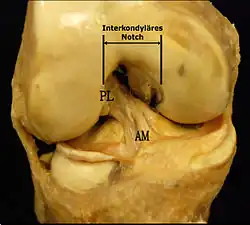

Les facteurs anatomiques sont soupçonnés déjà depuis longtemps. La résistance à la rupture d'un LC dépend directement de sa largeur, qui varie d'un individu à l'autre. Dans une étude anthropométrique, les LCA du genou controlatéral intact de patients victimes d'une rupture de LCA ont été comparés avec ceux d'individus de même poids corporel. Les volumes des LC ont été déterminés par IRM. Dans le groupe des blessés, le volume des LCA contralatéraux était en moyenne 1 921 mm3, tandis que dans le groupe de contrôle, il était de 2 151 mm3. Les auteurs de l'étude en concluent que les différences anthropométriques des volumes – et de la largeur qu'on en déduit – des LC ont une influence directe sur la probabilité d'une rupture de LC sans agression externe[49]. Déjà dans des études précédentes, on a établi une corrélation entre cavité ligamentaire du fémur (notch intercondylaire : voir figure) étroite, liée à des ligaments plus étroits, et un risque plus élevé de rupture de LC[50],[51],[52],[53],[54],[55]. Cependant on n'est pas arrivé à un consensus scientifique, parce que d'autres études aboutissent à des résultats opposés[43],[56],[57]. Par rapport aux hommes, les femmes ont une cavité ligamentaire plus étroite, ce qui pourrait expliquer une incidence plus élevée des ruptures de LC chez les femmes[58],[59].